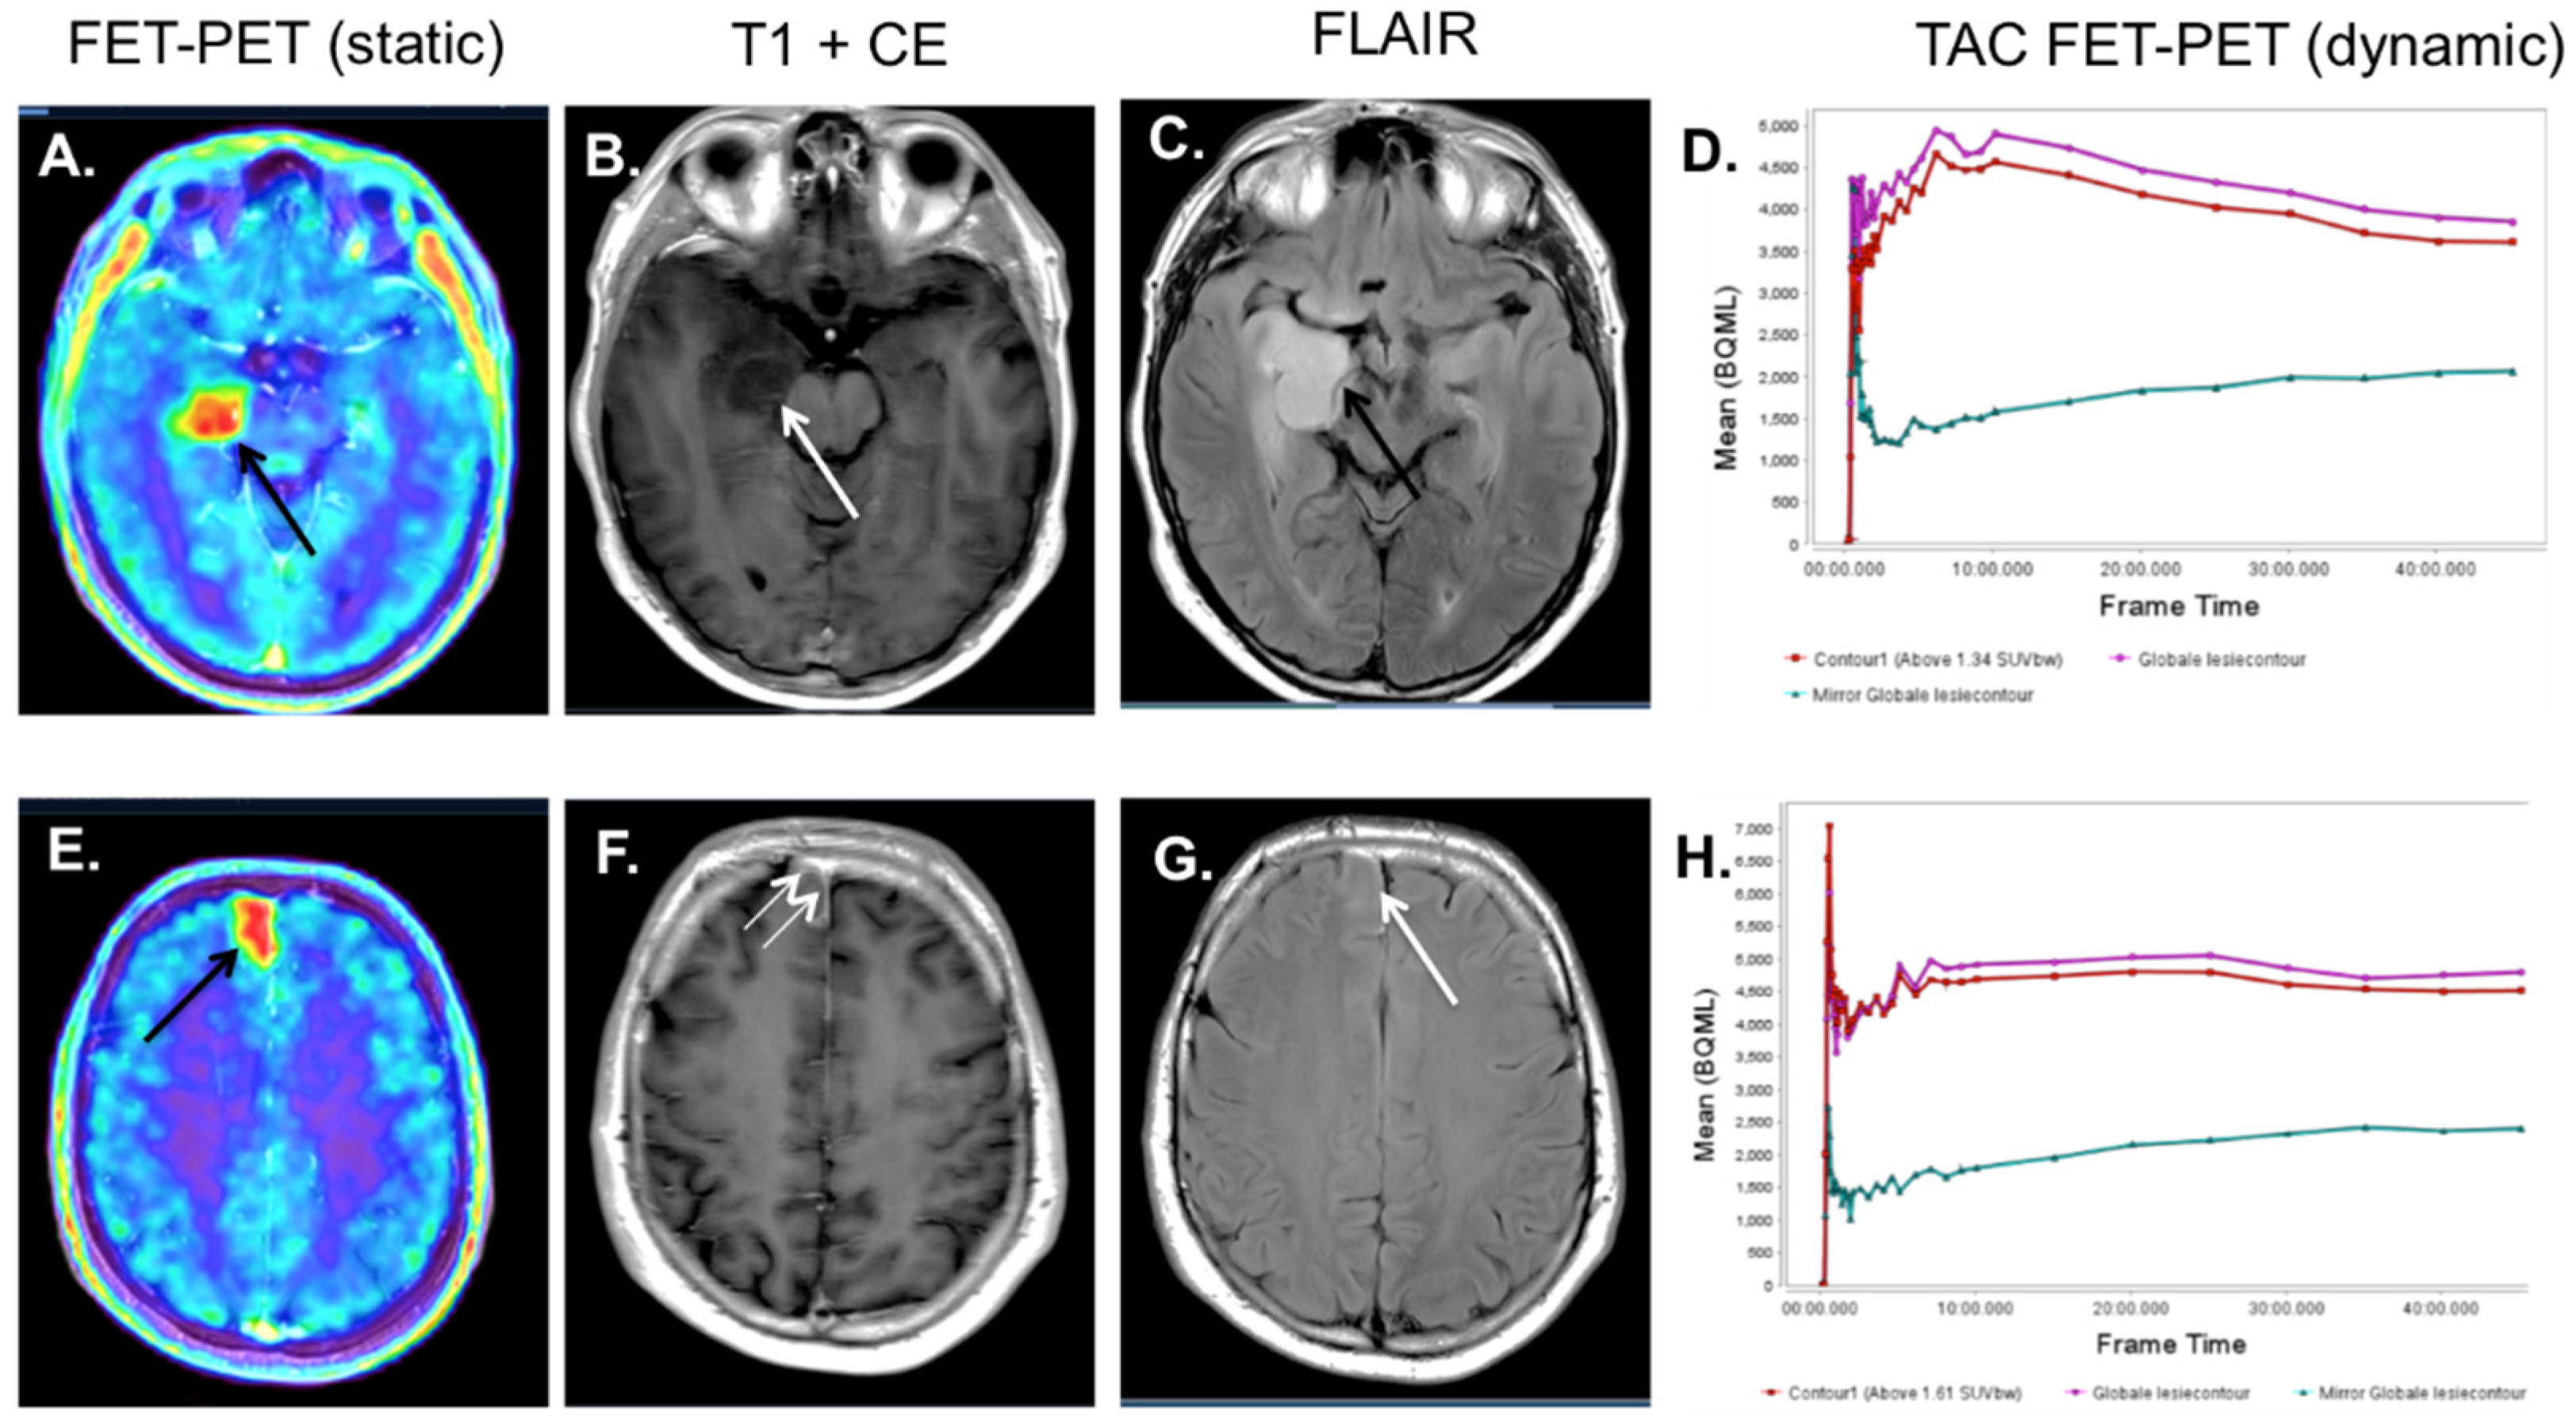

4. 18F-FET-PET-MRI